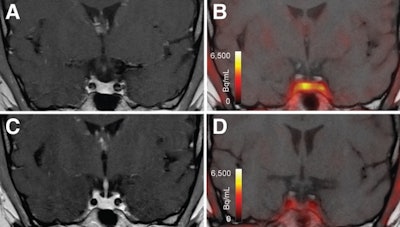

T1-weighted postgadolinium MR images (A and C) and F-18 FET-PET/MR images (B and D) centered at pituitary before (A and B) and after (C and D) transsphenoidal surgery. This patient with Cushing disease showed clear focal uptake (B) but no clear lesion on previously obtained and accompanying MRI (A). Postoperative tissue analysis did confirm resection of small pituitary adenoma/PitNET, and postoperative F-18 FET-PET showed no residual uptake (D). Image courtesy of the Journal of Nuclear Medicine.